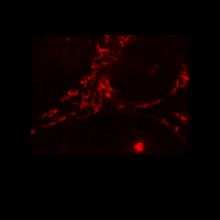

Mitochondria

세포내에 존재하는 미토콘드리아를 특이적으로 염색하여 실시간으로 그 위치와 상태를 시각화 할 수 있습니다. 미토콘드리아의 대사 변화, 약물의 독성 평가, 세포의 사멸, 미토콘드리아 동태 연구에 활용 됩니다.